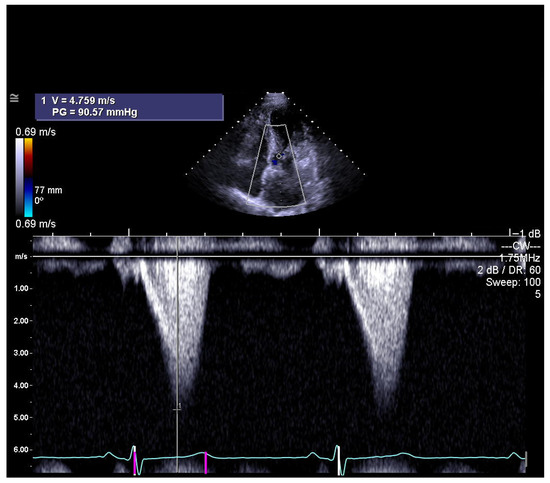

Global guidelines emphasize that septal reduction therapy (SRT) should only be performed in high-volume, specialized centers with experienced multidisciplinary heart teams to ensure the best outcomes. There is strong consensus regarding its indications in patients with obstructive hypertrophic cardiomyopathy. SRT is reserved for individuals who continue to experience significant symptoms—most often NYHA Class III–IV limitations such as severe shortness of breath or angina—despite optimal or maximally tolerated medical therapy. Across all recommendations, a peak left ventricular outflow tract (LVOT) gradient of ≥50 mmHg, whether at rest or during physiologic provocation, is considered essential (Figure 1). Additional requirements include systolic anterior motion (SAM) of the mitral valve and sufficient anterior septal thickness to allow safe procedural intervention. When determining the specific modality of SRT, guidelines consistently prefer surgical septal myectomy, especially for patients who also need surgical correction of other cardiac conditions. In cases where surgery is contraindicated or carries excessive risk, alcohol septal ablation (ASA) is endorsed as the alternative [1,2].

Figure 1.

The left ventricular outflow tract (LVOT) shows a maximum gradient, usually with a late systolic peak, as assessed by continuous-wave Doppler echocardiography (photo and copyright: T.P.). PG—peak aortic valve gradient; V—maximum aortic valve velocity.